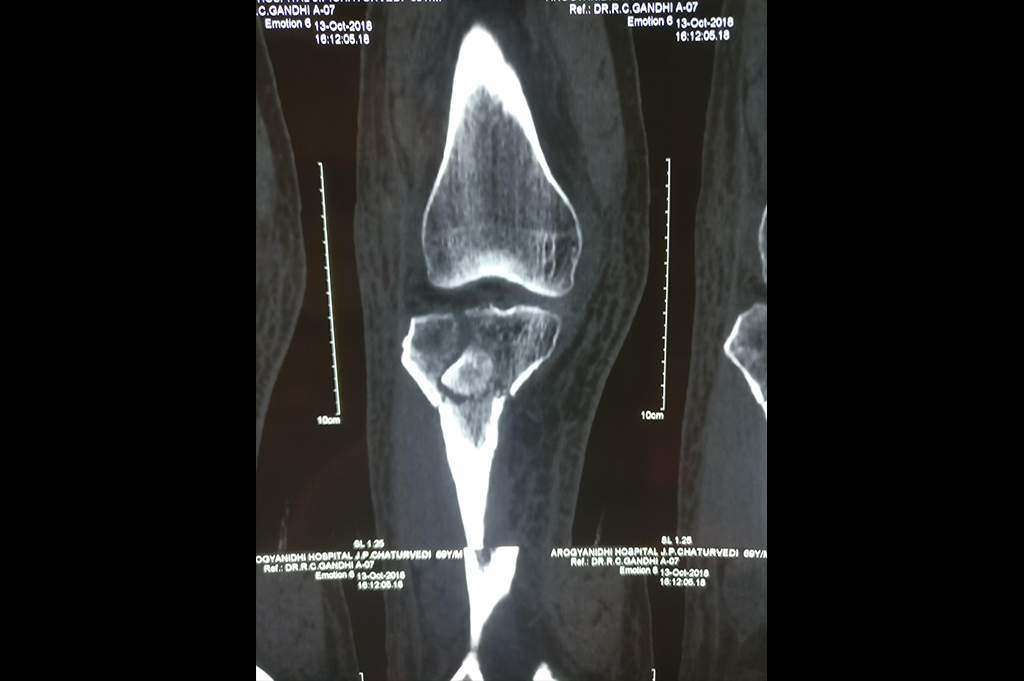

Distal Femur

Proximal Tibia